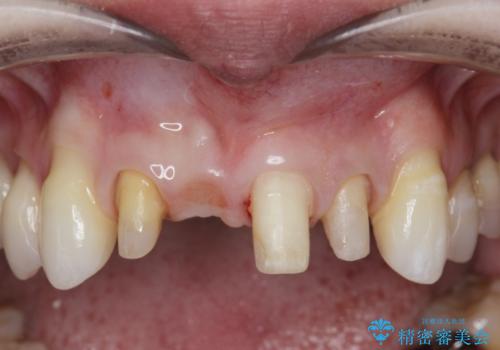

CT撮影を行った結果、右上前歯は吸収が進み抜歯が必要な状態です、

抜歯をせず放置すると、より吸収が進み臨在する歯にも悪影響を及ぼしてしまう可能性が考えられます。

上顎4前歯は、根管治療の既往があり、虫歯も見られたことからブリッジによる治療で審美性の回復を行うとともに臨在歯の虫歯もセラミック治療を行っていきます。